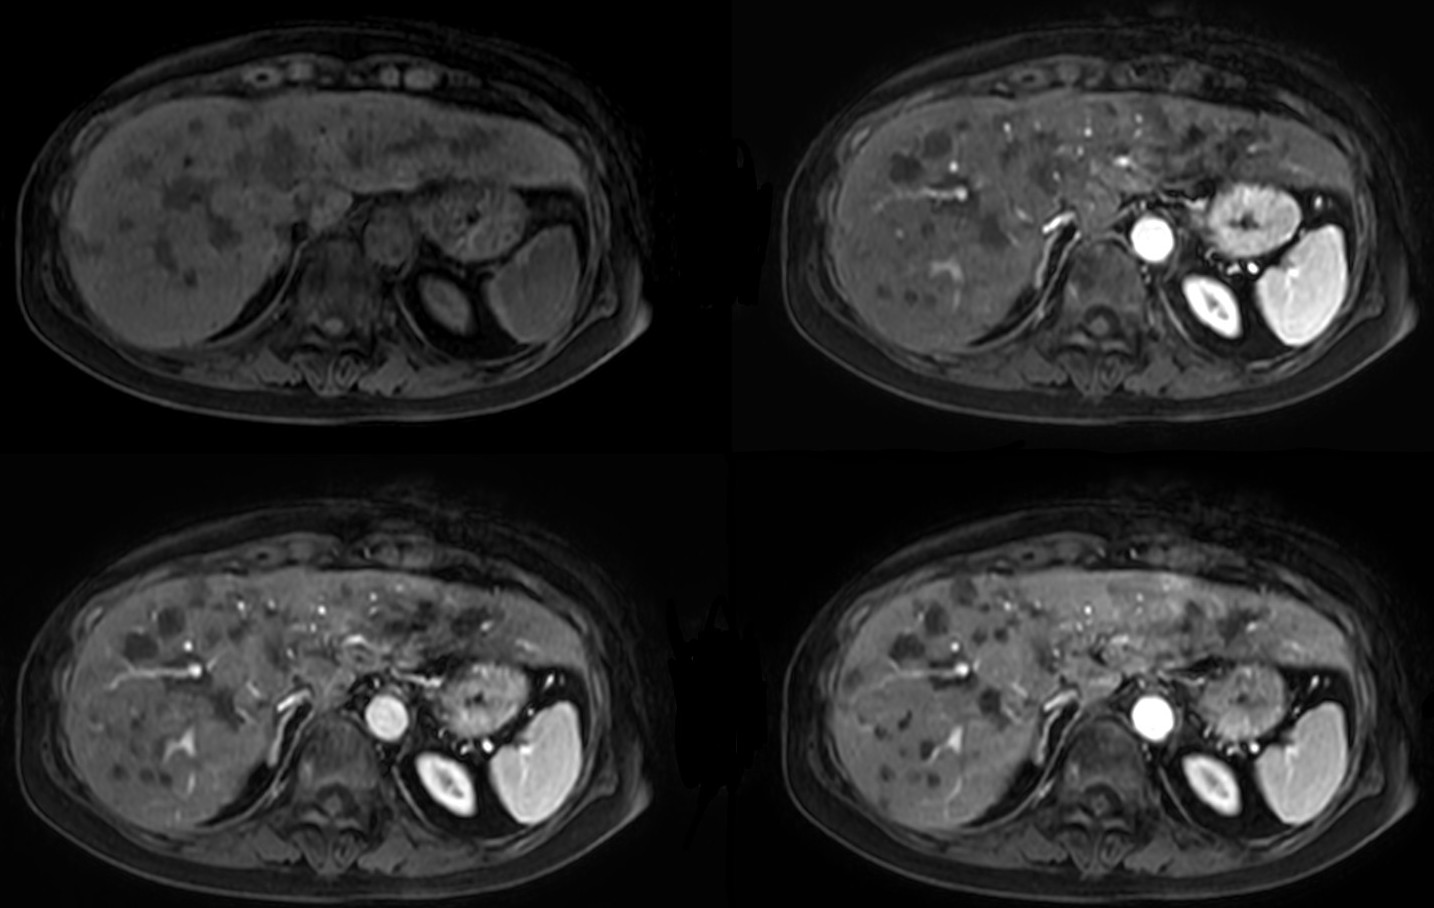

Liver metastasis with SmartSpeed Precise

Axial Dynamic eTHRIVE

Axial eTHRIVE 90 sec Post gado

Axial eTHRIVE 2 min Post gado

Axial eTHRIVE 3 min Post gado

Axial eTHRIVE 15 min Post gado